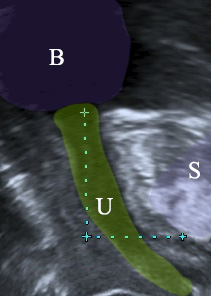

Η ουροδόχος κύστη εκκενώνεται μέσω της ουρήθρας. Πρόκειται για μια σωληνοειδή κατασκευή με μήκος περίπου 2.5-4 εκατοστών, η οποία χρησιμεύει στην αποβολή των ούρων. Πέραν όμως αυτής της της ιδιότητας, έχει γύρω της ένα σύμπλεγμα 3 διαφορετικών μυών, γνωστό και ως σφιγκτηριακό σύμπλεγμα της ουρήθρας, το οποίο είναι κυρίως υπεύθυνο για την αύξηση της πίεσης εντός της αυτής.

Η άνοδος της πίεσης στην κύστη κατά τον βήχα στις υγιείς γυναίκες οδηγεί σε ταυτόχρονη, παρόμοια αύξηση της πίεσης εντός της ουρήθρας, καθώς και τα δύο όργανα συμπιέζονται κόντρα στο υπόστρωμά τους, γνωστό και ως ηβοτραχηλική περιτονία. Έτσι η πίεση στην ουρήθρα παραμένει υψηλότερη εκείνης στην κύστη και η γυναίκα δεν χάνει ούρα. Αυτό το φαινόμενο λέγεται επαγωγή.

Αν όμως ο υποκείμενος ιστός της ουρήθρας έχει χαλαρώσει (ηβοτραχηλική περιτονία), τότε η ουρήθρα γίνεται υπερκινητική. Κάθε φορά που η ασθενής βήχει, η ουρήθρα “ξαπλώνει” και η πίεση εντός αυτής δεν μπορεί να αυξηθεί – έτσι η λεγόμενη επαγωγή της πίεσης αποτυχαίνει. Η πίεση εντός της κύστης αυξάνεται ραγδαία, εκείνη εντός της ουρήθρας όχι, έτσι η πρώτη υπερνικά τη δεύτερη και έχουμε τη δυσάρεστη απώλεια ούρων.